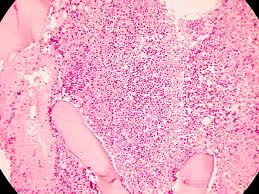

Información: El síndrome mieloproliferativo crónico es un conjunto heterogéneo de neoplasias hematológicas que tienen como característica común la proliferación descontrolada de los precursores medulares de alguna de las células sanguíneas animales, incluyendo los humanos. Por lo común, afectan la maduración de dichos precursores en fases avanzadas de la diferenciación, como dato diferencial con respecto a los síndromes mieloproliferativos agudos. El concepto de enfermedad mieloproliferativa fue propuesto por primera vez en 1951, por el hematólogo William Dameshek.

La incidencia de policitemia vera es de aproximadamente 0.02-2.8 por cada 100,000 habitantes cada año, siendo Japón el país con la menor incidencia.2 La trombocitopenia esencial tiene una incidencia mayor, cercana a 0.1-1.5 por cada 100,000 habitantes cada año. La mielofibrosis, por su parte, tiene una incidencia internacional de aproximadamente 0.4-0.9 por cada 100,000 habitantes cada año. La mortalidad y morbilidad exactas no son conocidas.

La leucemia mieloide crónica tiende a afectar a todas las razas por igual. La incidencia de policitemia vera, trombocitopenia esencial y mielofibrosis es 10 veces mayor entre judíos askenazíes del norte de Israel que personas de descendencia de la región arábica.2 La relación hombre y mujer es de aproximadamente 1:1.4. La mayoría de los casos clínicos se encuentran en pacientes entre las edades de 40-60 años. Las enfermedades mieloproliferativas no son comunes en personas menores de 20 años y son muy raras en la infancia.